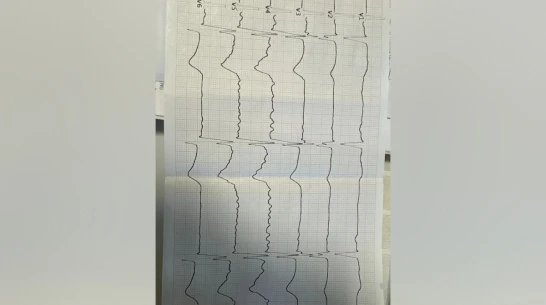

У пациента были жалобы на боль в груди, повышенную утомляемость при физических нагрузках и чувство нехватки воздуха. Медики установили предварительный диагноз – ишемическая болезнь сердца, нестабильная стенокардия. Благодаря терапии врачам удалось купировать болевой синдром и одышку, однако на следующий день у мужчины внезапно остановилось сердце. Пациенту сразу же оказали помощь, после чего его перевели в палату интенсивной терапии. Ночью того же дня сердце мужчины остановилось еще раз, но его вновь спасли, проведя сердечно-легочную реанимацию и электроимпульсную терапию. После того как состояние воронежца стабилизировалось, ему также провели плановую коронарографию. Сейчас пациент уже выписан, продолжает амбулаторное лечение и хорошо себя чувствует.